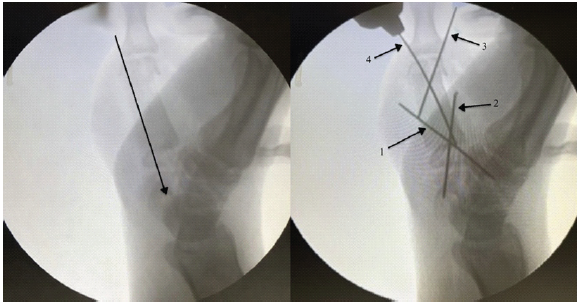

Under a supraclavicular block regional anesthesia, the patient was positioned for surgery, and a tourniquet was applied to the upper arm. A lazy-S incision was made over the base of the right thumb to provide adequate exposure. Dissection was carefully carried down to the level of the metacarpal, preserving surrounding soft tissues and neurovascular structures. A wide local excision of the tumor with preservation of the endplates of the 1st metacarpal both proximally and distally, with a thickness of 5 mm, was performed. After excision, we curated the end plate. The excised mass measured approximately 4.6 cm (Fig. 3 and 4).

Figure 3: Intraoperative c-arm Image

A tricortical ICBG was harvested, measuring 5 cm, and the edges were smoothed, locked, and aligned into the end plate to fit the metacarpal defect as an en bloc graft within the resected area. First, a temporary K-wire of 1 mm was passed through the ICBG in a distal-to-proximal direction. Once the graft was positioned at the defect site, the wire was advanced to achieve fixation with the trapezium and scaphoid. Following that, the 1st and 2nd K-wires were inserted from distal to proximal in a cross configuration crossing from the graft, proximal end plate, and then the carpal bone. The temporary wire, which was initially placed, was removed. Then, the 3rd K-wire was inserted from the ulnar side, crossing the distal end plate and the graft. Finally, the 4th K-wire was inserted from the radial side, crossing the distal end plate and the graft. All the K-wires were cut and buried; wound closure was done (Fig. 4).